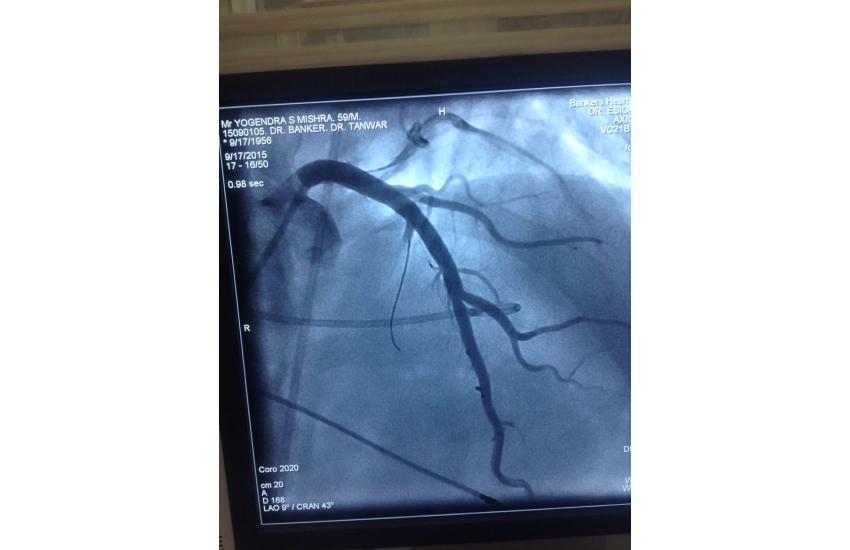

CAG revealed normal coronaries,holter shows sinus bradycardia,RBBB with LAHB,intermittent AF, TMT shows blunted chronotropic response and hypotensive response so he has been planned for PPI with back up of pacemaker patient treated with beta blockers and corderone,after 7 days of PPI,he has undergone alcohol septal ablation successfully,prior his dynaemic gradient was 50 mmhg in rest n 80 mmhg with exercise which reduced to 20mmhg after procedure. Now patient is under close follow up so will continue updating.